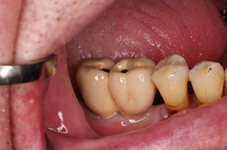

Během let může postupnou ztrátou zubů zůstat v ústech omezený počet zubů, které umožňují držení zubních náhrad.

V důsledku přetížení zbylých zubů např. houpavými pohyb snímacích náhrad dochází k uvolnění těchto zubů a držení můstků a protéz je tak velmi těžké. V těchto případech můžeme pomocí implantátů zvýšit počet pilířů a tím zabránit přetěžování a ztrátě zbylých zubů